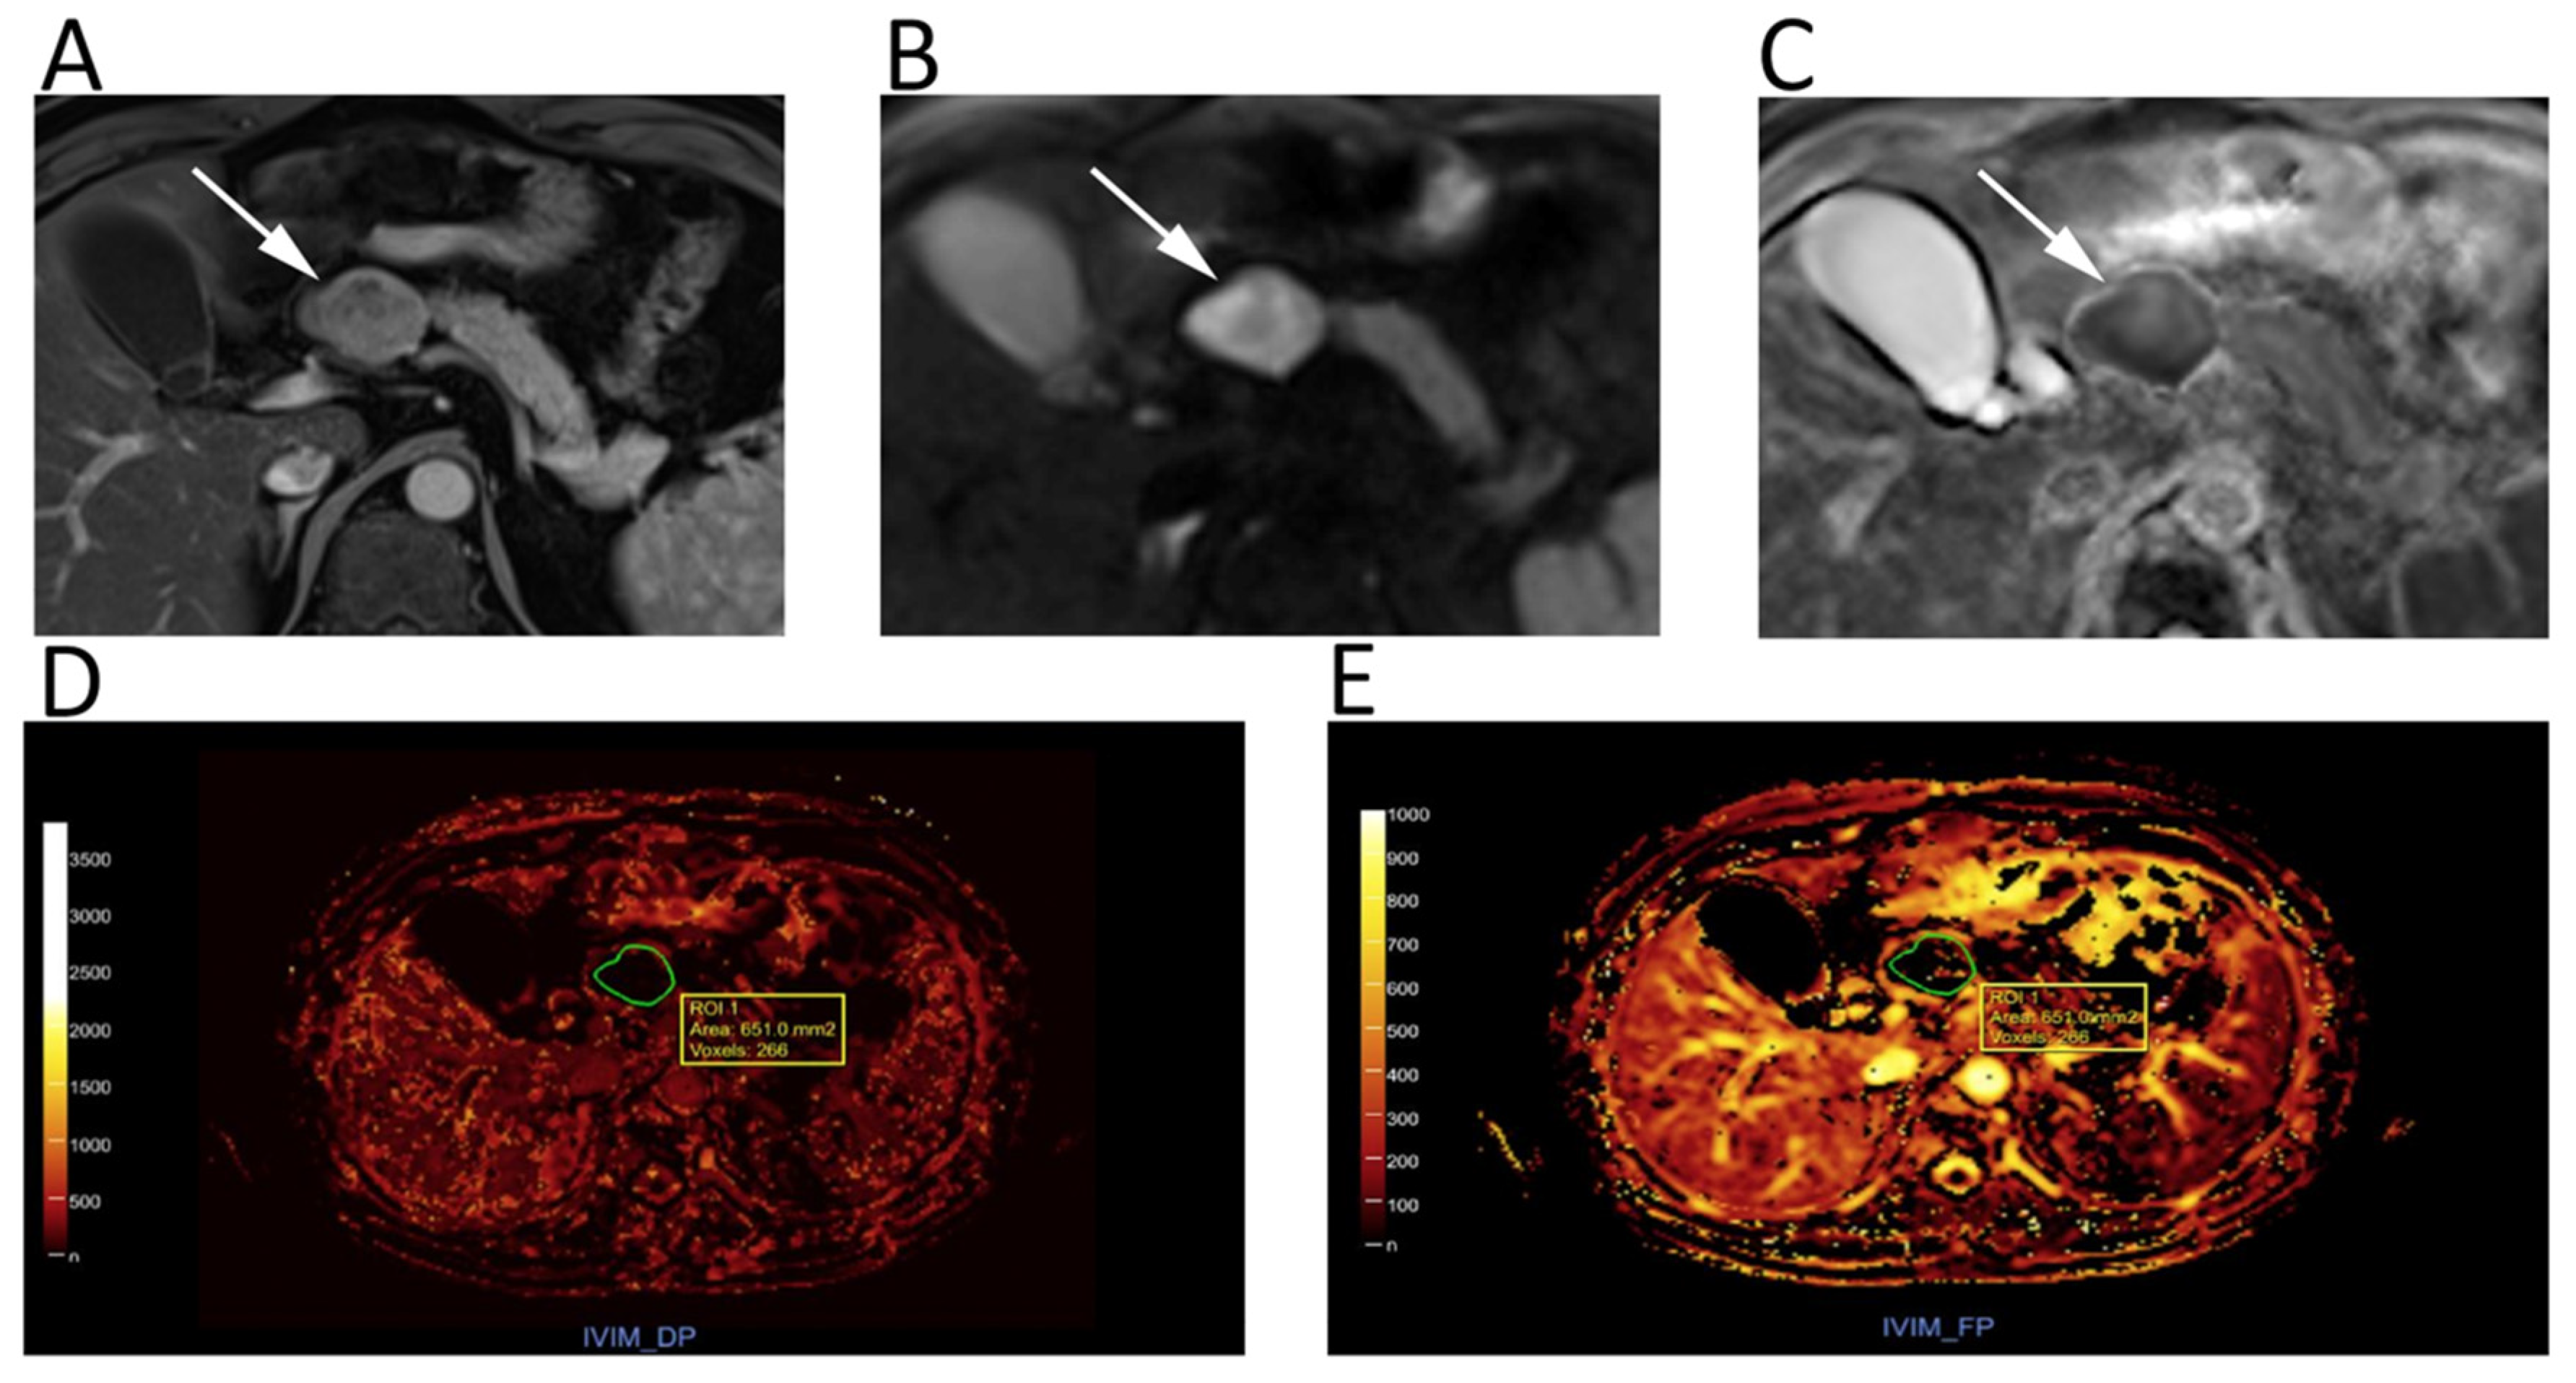

DWI is widely adopted as a part of pancreas MRI protocol. Pancreatic tumors, even if small, almost invariably show diffusion restriction, presenting as focal hyperintense areas on high-b-value DWI with corresponding low ADC. Previous studies reported high diagnostic performance for identification of pancreatic ductal adenocarcinoma using DWI, with reported accuracy, sensitivity, and specificity of 96%, 96%, and 99%, respectively [40,41]. Similarly, Kartalis et al. found very high diagnostic performance of DWI (92% sensitivity, 97% specificity, 96% accuracy) to differentiate malignant (mean ADC 1.4 ± 0.3 × 10−3 mm2/s) from benign (2.57 ± 1.17 × 10−3 mm2/s) pancreatic lesions [42]. Notably, the DWI appearance of PDAC can be very similar to that of autoimmune pancreatitis, which presents as a focal pancreatic enlargement with even lower ADC, due to fibrosis and inflammatory cell infiltration [40,41]. DWI has been also found to improve the detection of pancreatic neuroendocrine neoplasms (pNENs) [40]. Nevertheless, concurrent chronic pancreatitis may represent a confusing factor for the identification of pancreatic lesions [41]. Further, the differentiation of benign and malignant pancreatic lesions based only on ADC quantification is not so straightforward because of a wide overlap of ADC values [40,41]. Controversial results were also found to differentiate cystic lesions by means of DWI alone [40]. More consistent results have been described by using IVIM-DWI (Figure 6): perfusion-related parameters (i.e., perfusion fraction and fast component of diffusion) showed excellent inter-observer agreement and accuracy for identifying solid pancreatic lesions, and distinguishing malignant from benign intraductal papillary mucinous neoplasms [40,41].

Figure 6.

Upper abdomen MRI of a patient with G2 pancreatic neuroendocrine neoplasm. A heterogeneous hypervascular lesion (arrows) with well-defined margins can be seen on the axial arterial phase image (A). The lesion is clearly hyperintense on b = 800 DWI (B), with low ADC values on the corresponding ADC map (C). IVIM maps show that the tumor has low values of fast diffusion (D) Dp, but relatively preserved perfusion fraction (E) Fp, consistent with a neuroendocrine neoplasm.